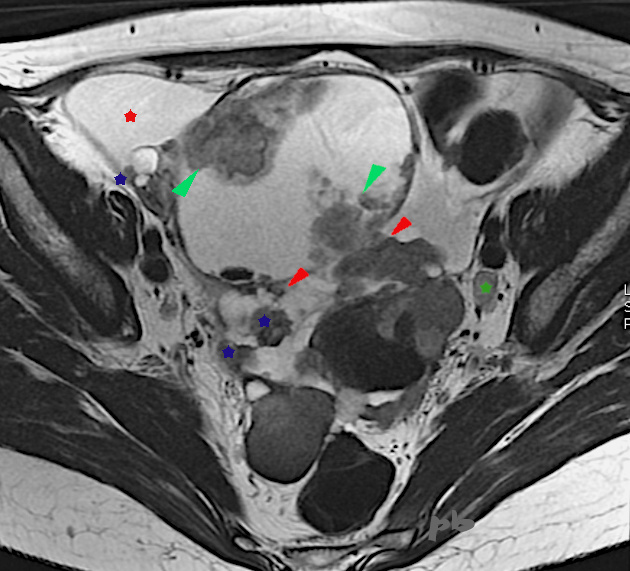

IRM axial T2

10 mois plus tard, récidive du kyste droit.

Volumineux kyste à droite, contenant des végétations internes (►) et externes (►).

Les zones tissulaires s’étendent sur le péritoine (★). On en retrouve en particulier en sus-vésical et dans le Douglas (non montrées).

Ascite (★).

Adénopathie iliaque gauche (★)

Prise de contraste après injection de gado.

Conclusion : Tumeur ovarienne maligne et carcinomatose péritonéale.